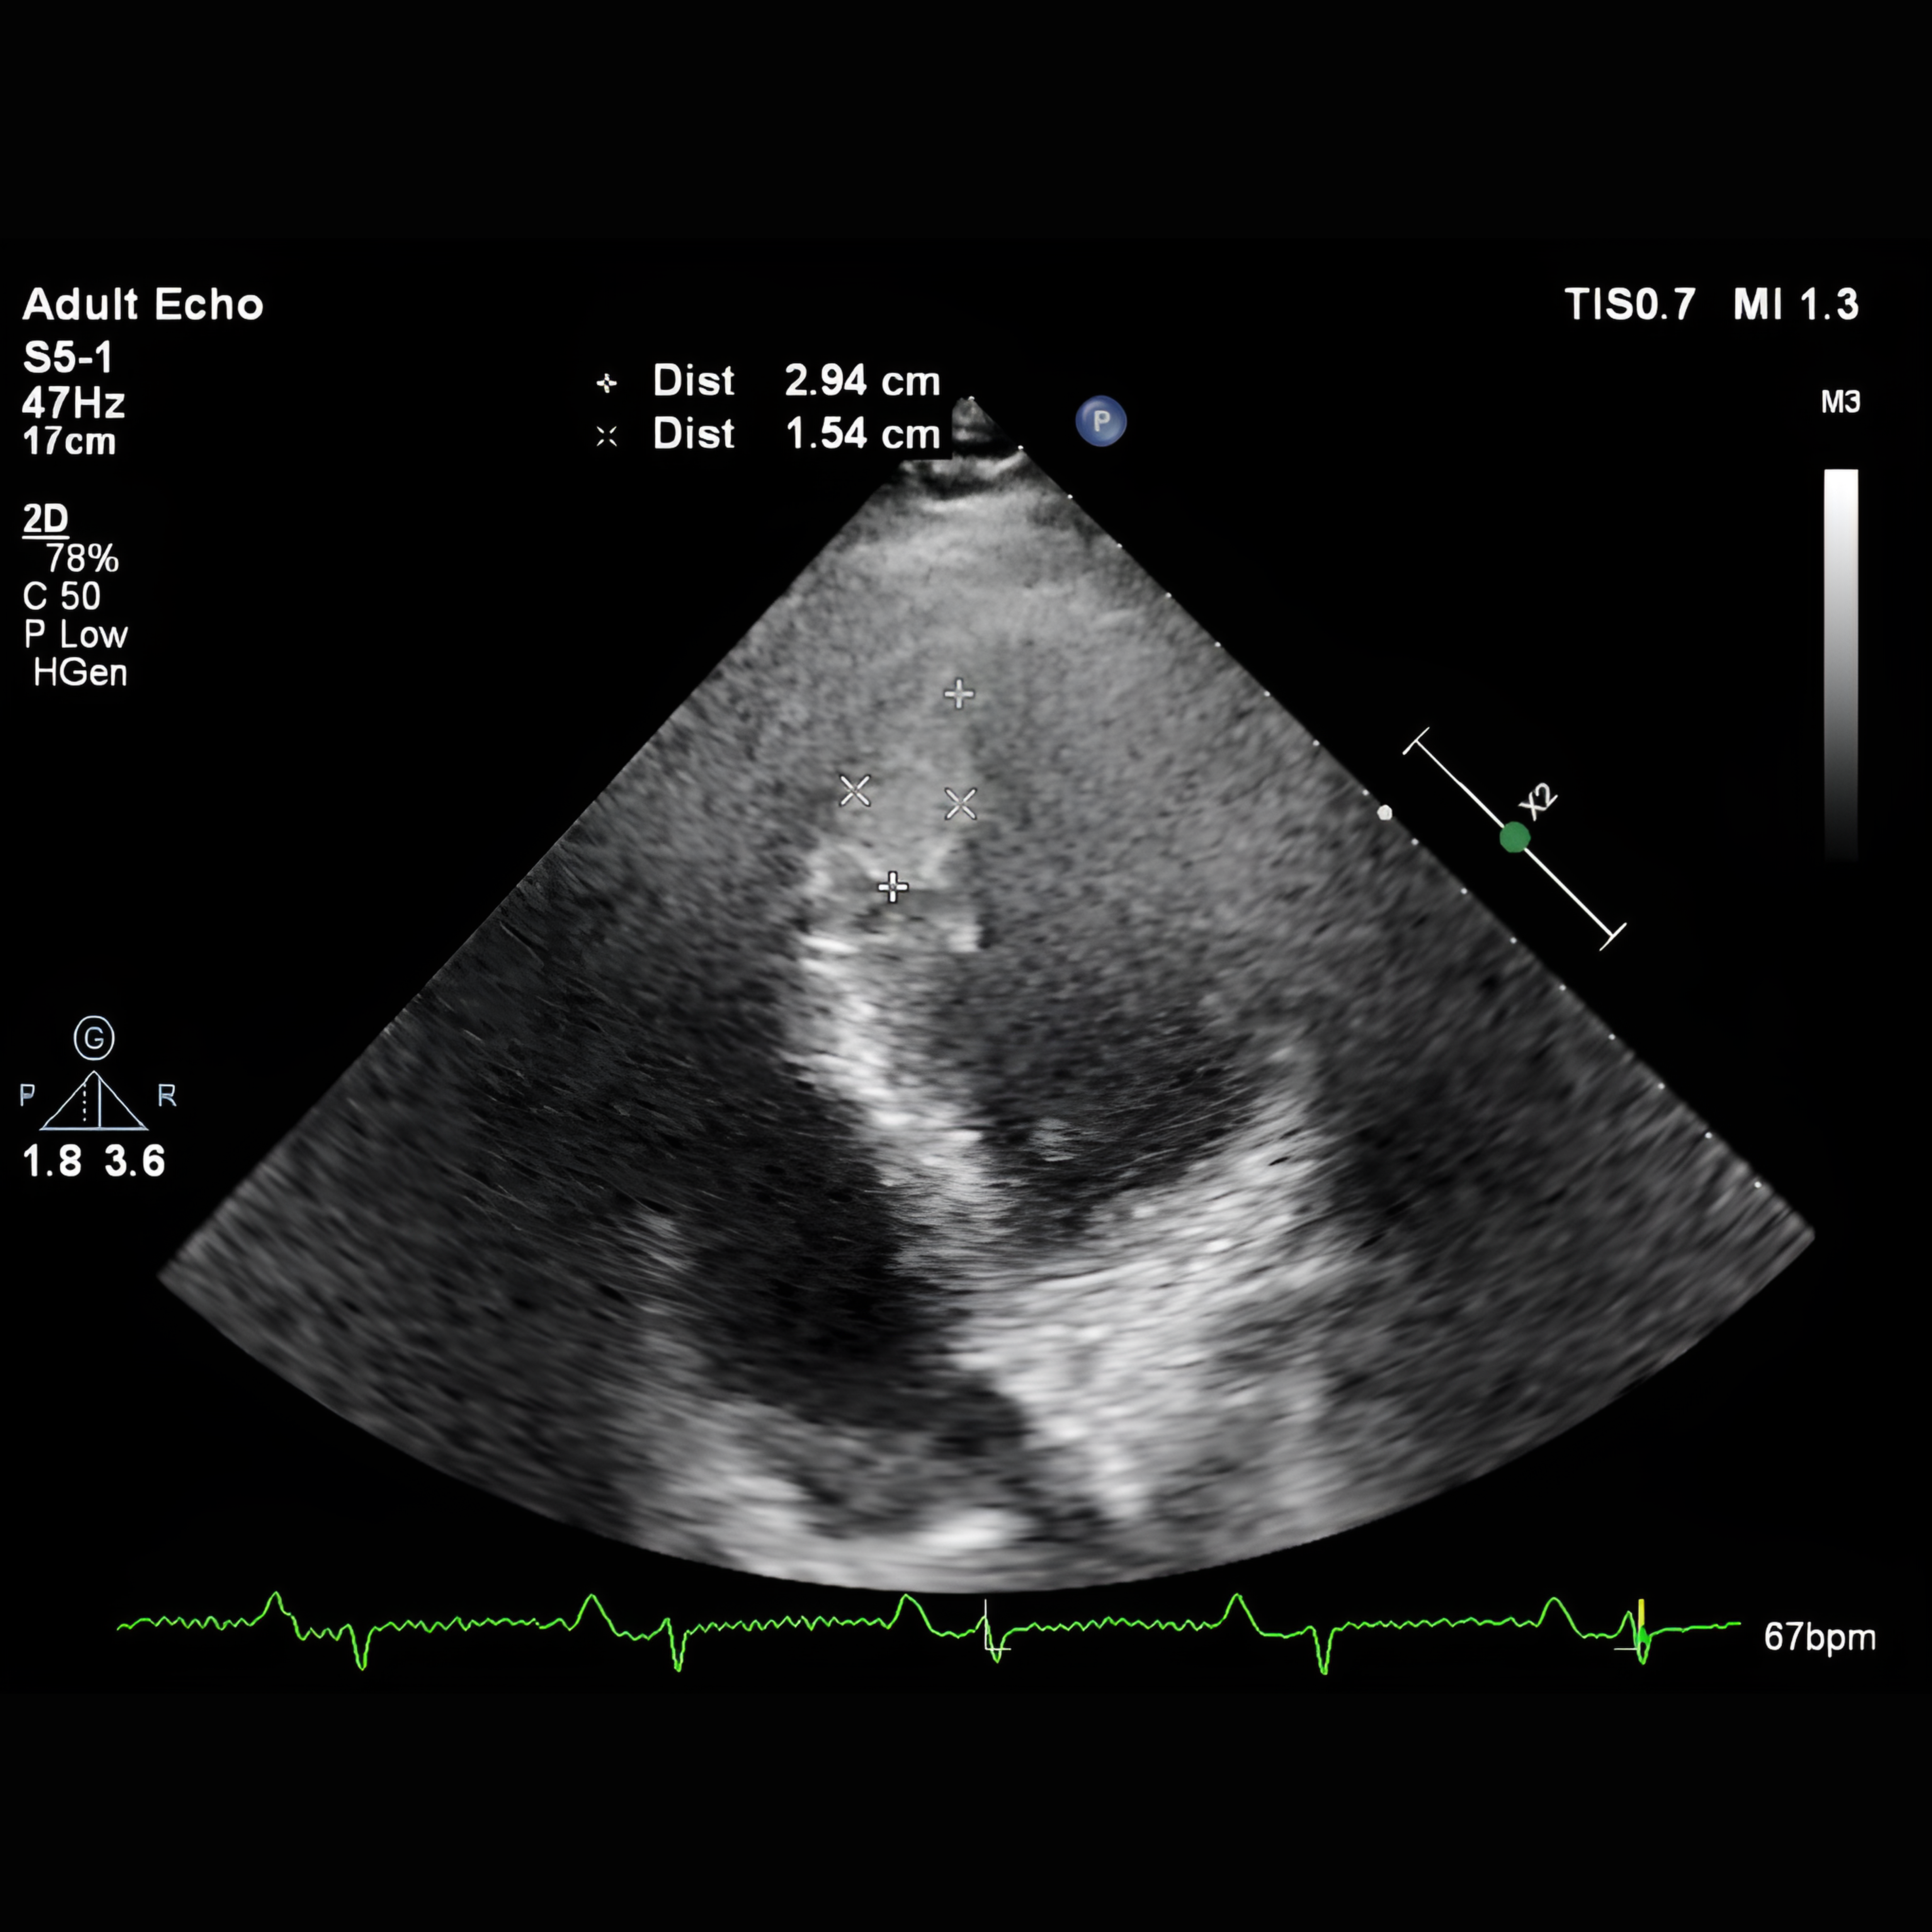

Relevant Test Results Prior to Catheterization

Laboratory testing revealed markedly elevated D-dimer (>3 g/mL). In case 1, the electrocardiogram (ECG) revealed atrial fibrillation accompanied by ventricular pacing spikes (Figure 2). CT angiography showed a total occlusion in the right brachial artery, which wasn¡¯t done in case 2 to prevent a higher contrast exposure. Echocardiography was performed to determine the source of embolism and found a large LV thrombus in the apical segment (Figure 3).